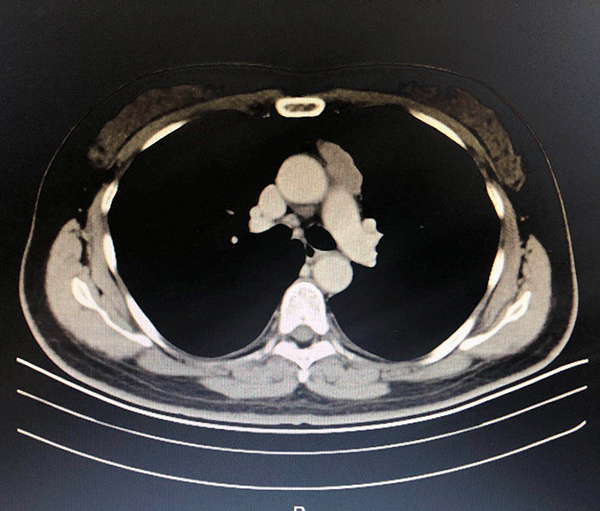

一年来,在副院长王钢与主任王剑飞的带领下,该中心通过对肺部小结节检查、诊断和治疗的一站式服务,旨在尽可能提升肺恶性结节的早期发现率、诊断准确率及治愈率。中心聘任浙大邵逸夫医院、上海肺科医院等专家,与院内骨干医生将轮流坐诊,同时联合肿瘤科、胸外科、呼吸内科和放射科等,为病患提供科学、安全的治疗方案。 “三对一”的特色诊疗方式——三位专家同时接诊一位病人,更有效地降低了漏诊及误诊率。

截止目前,中心共接诊患者800余人,完成120余例各项微创手术治疗,收获了众多患者及家属的感谢与信任,更树立起了良好的口碑。目前,他们主要开展的手术项目有: